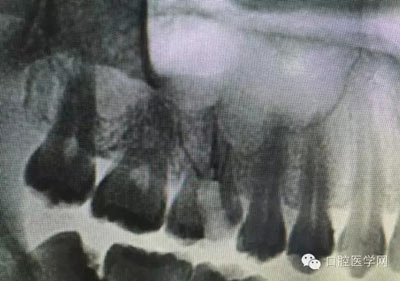

根管治療,我們在大學的時候就學習的東西,標準就在那里放著,可是很多時候我們熟視無睹,放任我們的想象去做。我們多些重視,多些心思,會好很多,認真對待每顆牙齒。